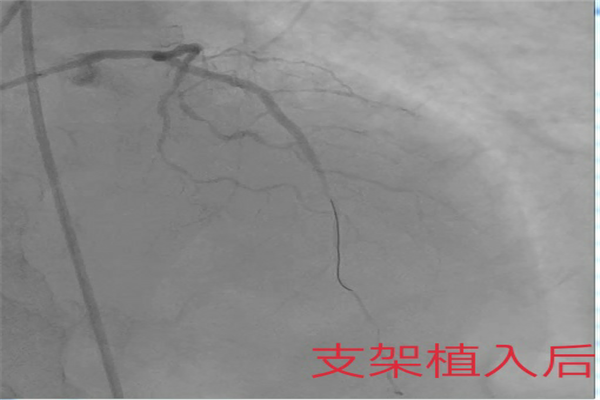

患者蘇某,男,61歲,因胸悶、胸痛入院,接診醫(yī)生高度重視,問診后隨即開辟綠色通道,急查心電圖提示:急性前壁心梗,立即平車護送患者至心內(nèi)科。由于該患者在院外耽誤時間過久,生命體征極不穩(wěn)定。心內(nèi)科徐曉輝主任立即調(diào)派人員,一邊組織人員搶救,一邊啟動導(dǎo)管室。各個人員都即刻到位,武衛(wèi)黨、耿蓬勃兩位副主任醫(yī)師在導(dǎo)管室為患者消毒、穿刺、造影一氣呵成,明確罪犯血管為前降支近端100%閉塞。即刻導(dǎo)絲通過,順利植入2枚支架,恢復(fù)冠脈血運?;颊叩腄toB(患者進入醫(yī)院大門至導(dǎo)絲通過閉塞的血管時間)僅僅為86分鐘。由于患者心臟梗死面積較大,血壓不穩(wěn),心源性休克,徐曉輝主任當機立斷,指示置入IABP泵保駕,患者病情有所好轉(zhuǎn),大家稍微放松一口氣。